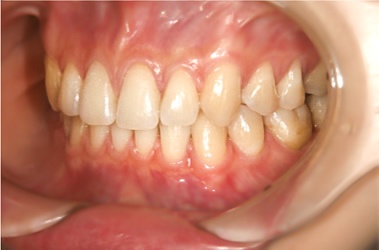

<受け口を治療した症例>

治療前

治療後